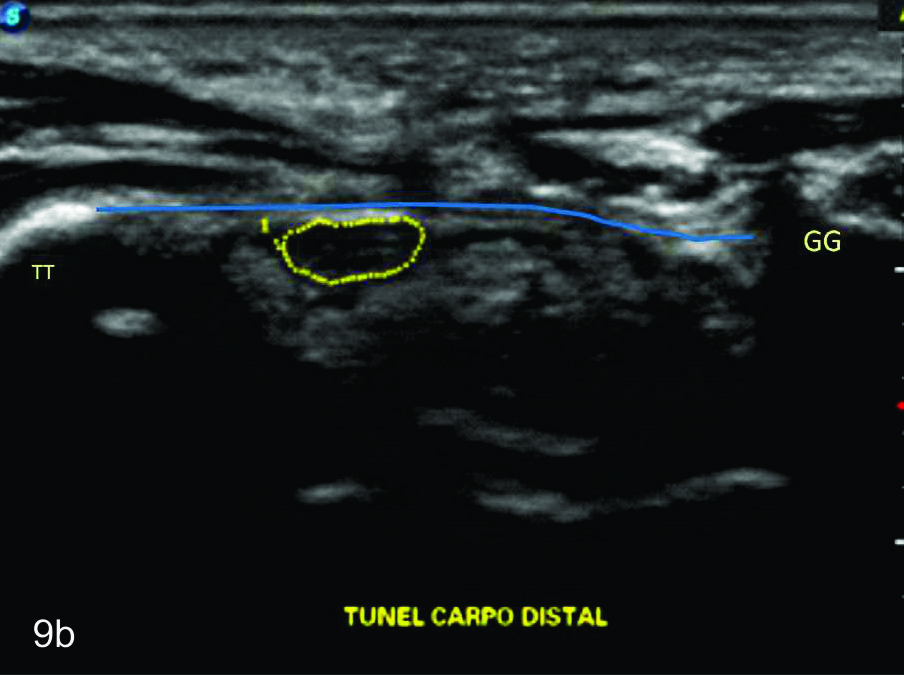

Figura 9

Nervio mediano

Cortes axiales en el nivel del túnel del carpo, se identifica al nervio mediano dentro de la elipse amarilla. A- Túnel proximal, al nivel del hueso pisciforme (P), B- Túnel distal, entre el túberculo del trapecio (TT) y el gancho del hueso ganchoso (GG). AC- Arteria cubital, NC- Nervio cubital, Línea azul- ligamento anular del carpo.